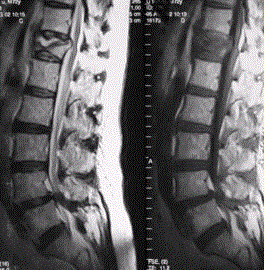

问题 患者男,70岁,因肝癌入院,准备行肝移植手术。住院期间因腰扭伤而腰痛,故行腰椎MRI检查(如下图)。 鉴别椎体良、恶性压缩性骨折,支持良性病变的征象有

选项 A.椎体前后径加长 B.椎体后缘弧形后凸 C.椎体内较均匀信号异常 D.椎体后缘平直 E.椎体后上角后翘 F.椎体内可见长T1长T2液体信号影 G.DWI序列椎体呈低信号 H.DWI序列椎体呈高信号

答案 DEFG